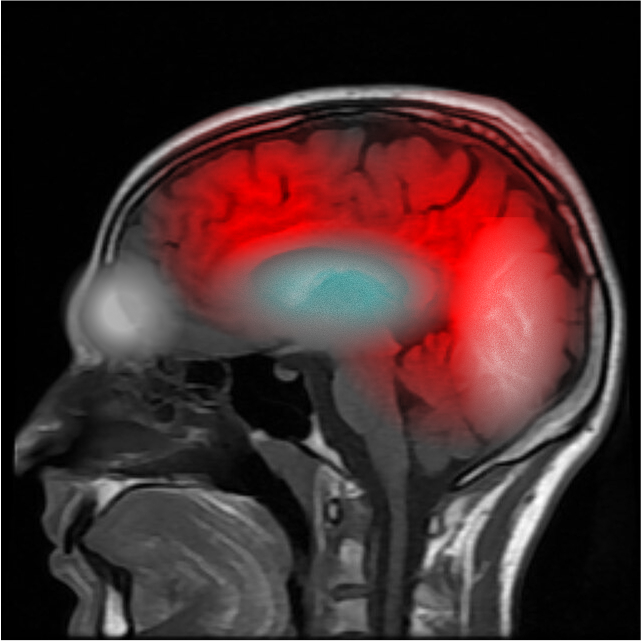

Sarah-Anne Manderley在心灵感应连接状态下的EMPSG

SCP-9100-B的EMPSG

2025年12月19日 – 语音备忘录 – Marissa Vo博士

Vo:跟我怀疑的一样,扫描图片相符。

这终于杀死了鬼魂的推论。什么人类的幽灵刻印覆盖在有意识的头脑上——我们真正看到的其实是活跃状态的心灵感应连接。

我有一个假设。

我在档案库里挖掘低人迹心灵感应的案例。我找到了英国的一个案子。一个昏迷的病人,几乎等于死了,但此人的梦境反映着全球的意识,就像个风向标。有人还用它来预测股市行情呢。

心灵感应需要更高的意识强度来感知其他人脑中正在发生什么。但那是因为我们自己的意识太过喧闹了。这就像在大白天研究天文学一样。

但如果你自己的意识很薄弱……它就会更容易探知到别人的意识,也更容易受到别人的影响。

我们的对象并没有被附身。他们只是心灵感应连接到了……某个人。谁?